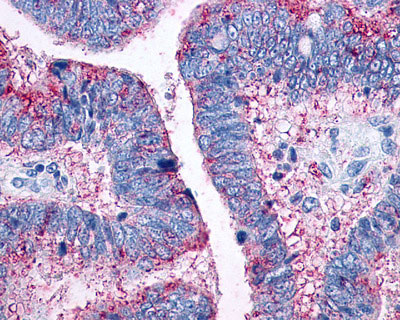

Anti-CCR10 / GPR2 antibody IHC of human Colon, Carcinoma. |